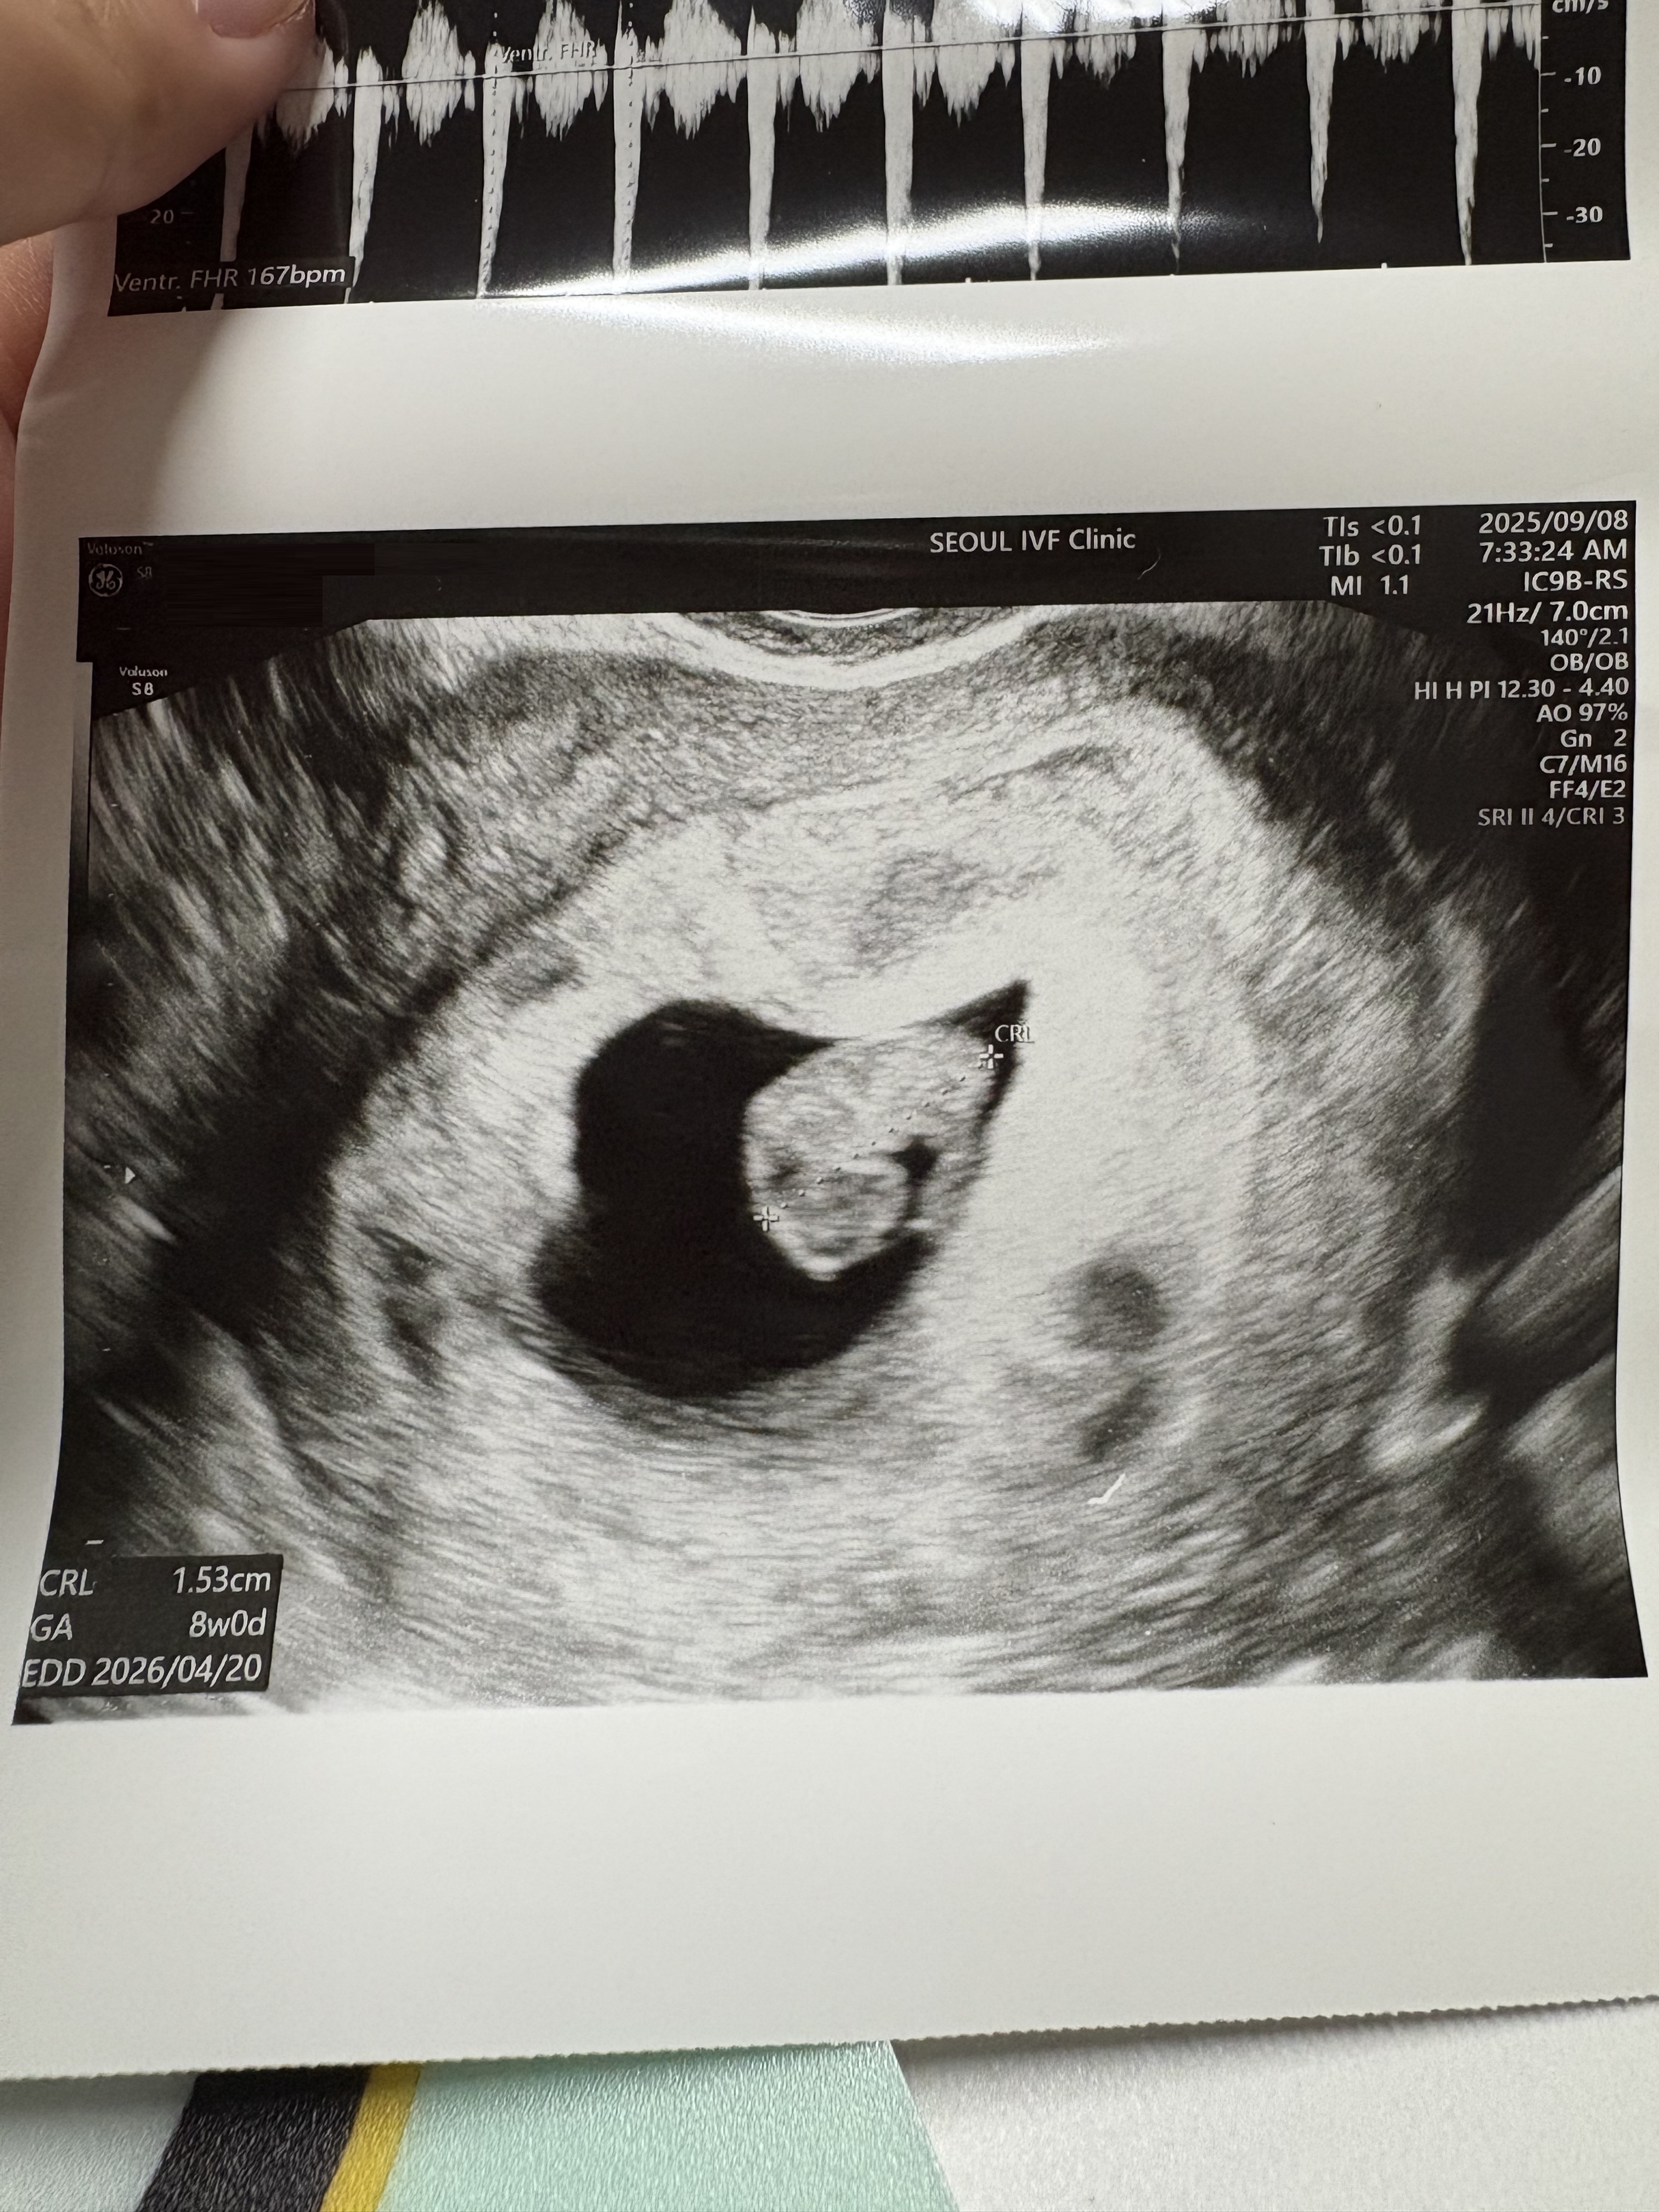

| 가슴 떨리는 임신 이야기를 공유해 주세요. | 임신은 새로운 생명이 자라나는 기적이에요. 처음 임신 사실을 알았을 때의 설렘, 초음파 속 아기 심장 소리에 가슴이 뛰던 순간, 작은 움직임을 느끼는 찰나까지… 모든 순간이 가슴 떨리고 벅찼어요. 이 과정은 사랑과 희망으로 가득한, 말 그대로 특별한 경험이었습니다. |

| 치료 도중 느꼈던 가장 기뻤던 순간과 절망적인 것들은 무엇인가요? 잊지 못할 경험이 있나요? | 이식 후 처음으로 임신 테스트기에서 두 줄을 확인했을 때, 말로 다 표현할 수 없을 만큼 기쁘고 행복했어요. 오랜 시간 기다려온 선물을 드디어 받은 느낌이라 지금도 잊을 수 없는 순간이에요. 하지만 그 기쁨은 오래가지 못했어요. 퇴근길 갑작스럽게 하혈을 하게 되었고, 결국 유산이라는 가슴 아픈 현실을 마주했습니다. 하늘이 무너지는 듯한 절망감이 아직도 생생해요. 잠깐 머물다 떠난 아이였지만, 제게 와주었던 그 순간만큼은 여전히 소중한 기억으로 남아 있습니다. |